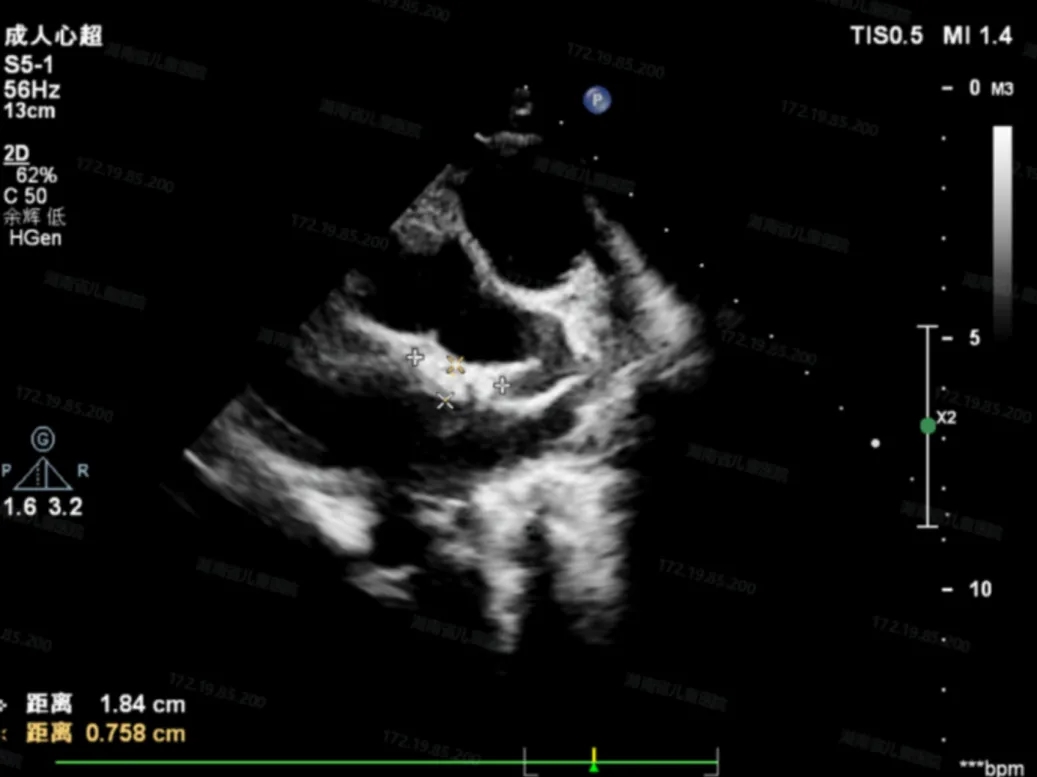

术后超声检查

超声下可见封堵器形态位置正确,未见明显血流通过,封堵器盘面贴合,位置固定